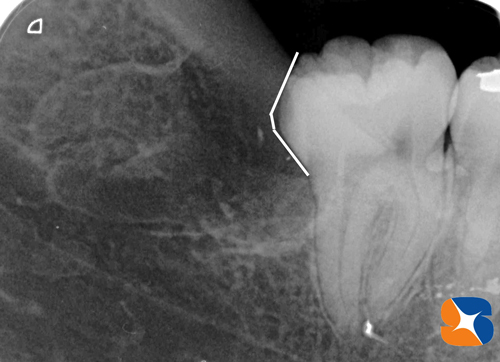

下顎の横向きの親知らず 根っこも湾曲早速CT撮影をして資料集め。横向きの親知らずが、太い神経の真上に横たわり、根っこは曲がりくねり、その手前の歯は奥へ大きく張り出し、そこに親知らずの頭がガッチリ食い込んでいる、といった具合でした。

根の先も曲がりくねっていて骨を抱きこむ まず向かって左の1本目。予想通りの曲がりくねった歯の根をしていました。こちらの抜歯で約1時間かかりました。

難易度の高い横向きの親知らずの抜歯抜いた痕のレントゲン写真。歯の頭を取り除くのに時間がかかりました。